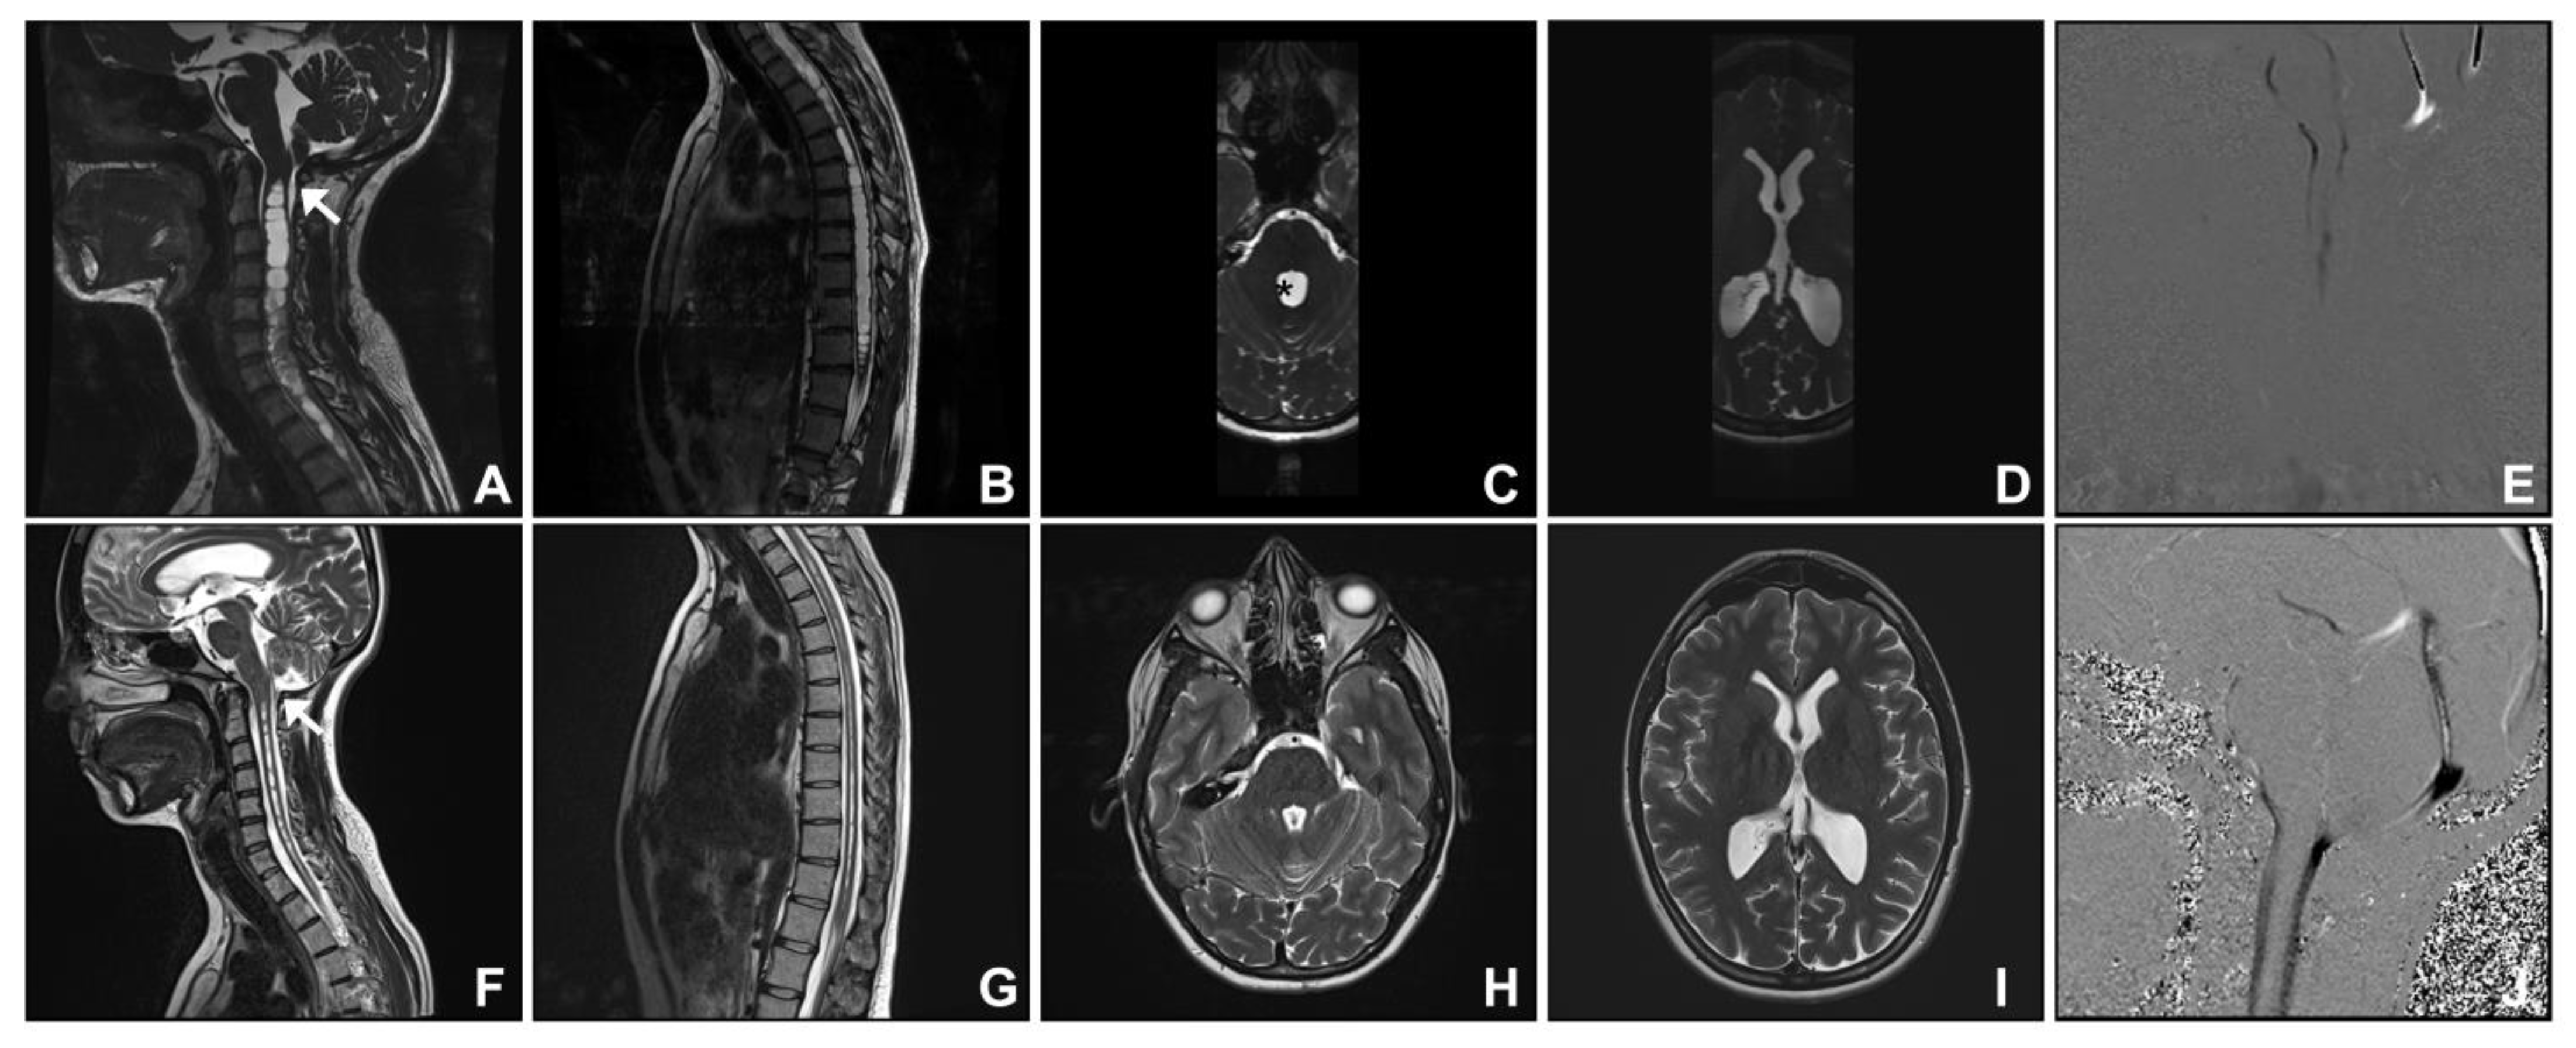

3.1. Group One. Post-Traumatic Cranio-Cervical Junction Arachnoiditis and Syringomyelia

| 1 | 62 | F | Balance and gait deterioration | 10 | Septa at cervico-medullary junction, syringomyelia | Posterior fossa decompression and insertion of fourth ventricle to spinal subarachnoid shunt | Stable |

| 2 | 26 | F | Cough-induced left upper limb sensory disturbance | 10 | Septa at cervico-medullary junction, holocord syringomyelia | Posterior fossa decompression and insertion of fourth ventricle to spinal subarachnoid shunt | Improved |